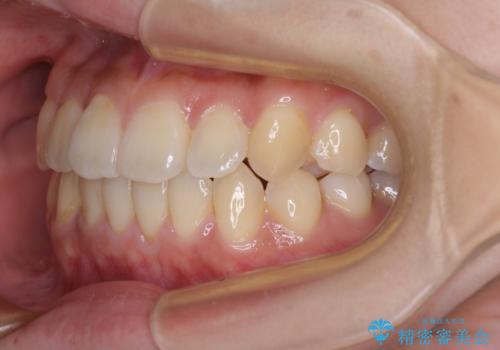

- 八重歯や前歯の捻転とクロスバイトが気になり、インビザラインによる矯正治療を希望して来院された患者様です。

上顎側切歯(上の真ん中から2番目の歯)が舌側転位している場合、無理して動かそうとすると歯髄壊死を起こすリスクが高い印象があります。

インビザライン単体でも治療は可能ですが、安全策としてインビザラインで歯列を移動する前に上顎前歯をワイヤー矯正で整え、その後上下歯列をインビザラインにて矯正治療を行うこととしました。

舌側転位している側切歯特有の、切縁の位置が不揃いであったり、根元が内側に引っ込んだ状態であったりという、インビザライン独特の仕上がりになることなく、きれいに整った歯列とすることができました。